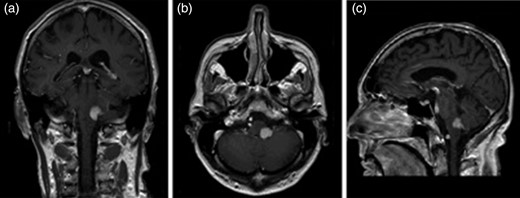

Gadolinium-enhanced magnetic resonance imaging (MRI) of the brain revealed a homogenously enhancing, sharply demarcated 13 mm diameter lesion in the left posterior and lateral midbrain extending into the inferior cerebellar peduncle, with some adjacent oedema, suggestive of primary lymphoma (see Fig. 1). Stereotactic brain biopsy confirmed diffuse large B-cell lymphoma (DLBCL) and subsequent bone marrow biopsy and computer tomography (CT) imaging showed no evidence of lymphoma at any additional anatomical site.

Gadolinium-enhanced T1-weighted MRI images (panes lettered with coronal (a), axial (b) and sagittal (c) sections) showing a homogenous enhancement of a clearly demarcated lesion in the left posterior and lateral midbrain with extension into the inferior cerebellar peduncle.